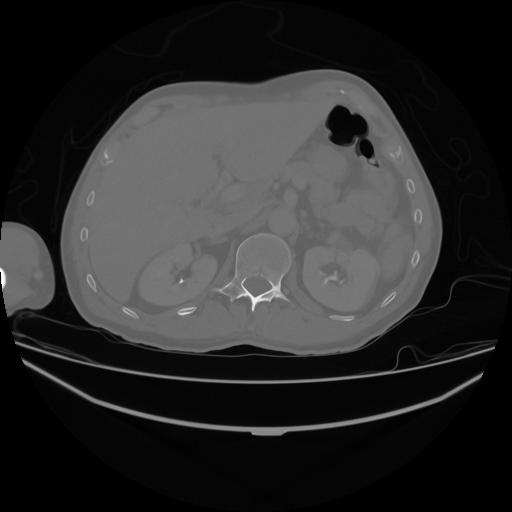

5 CUERPO,CE,Vol,1.0,CUERPO,,